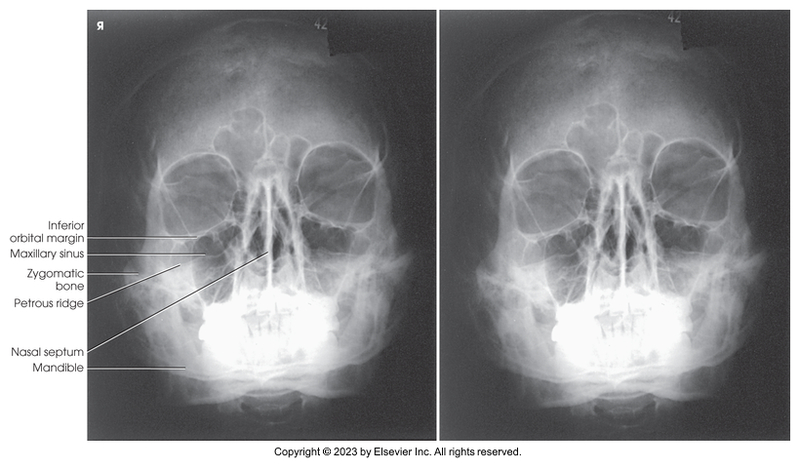

Parietoacanthial of facial bones - Waters method

Parietoacanthial of facial bones - Waters Method

Modified parietoacanthial of facial bones - Modified Waters method